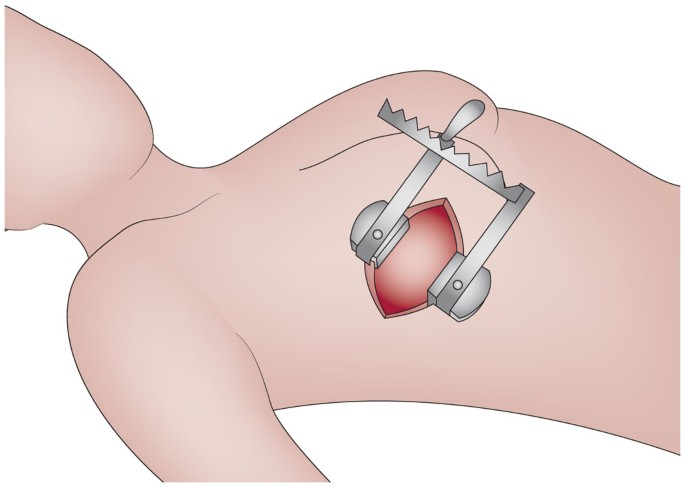

Open Heart Surgery

Valve Surgery

The heart’s valves play a vital role in controlling blood flow. When valves do not open or close properly, it can lead to serious health complications such as shortness of breath, fatigue, and chest pain. Valve surgery focuses on repairing or replacing these faulty valves to restore normal heart function. Dr. Pokharna specializes in both valve repair and replacement procedures, using advanced technology to provide long-term results. His expertise ensures improved quality of life for patients with valve disorders.